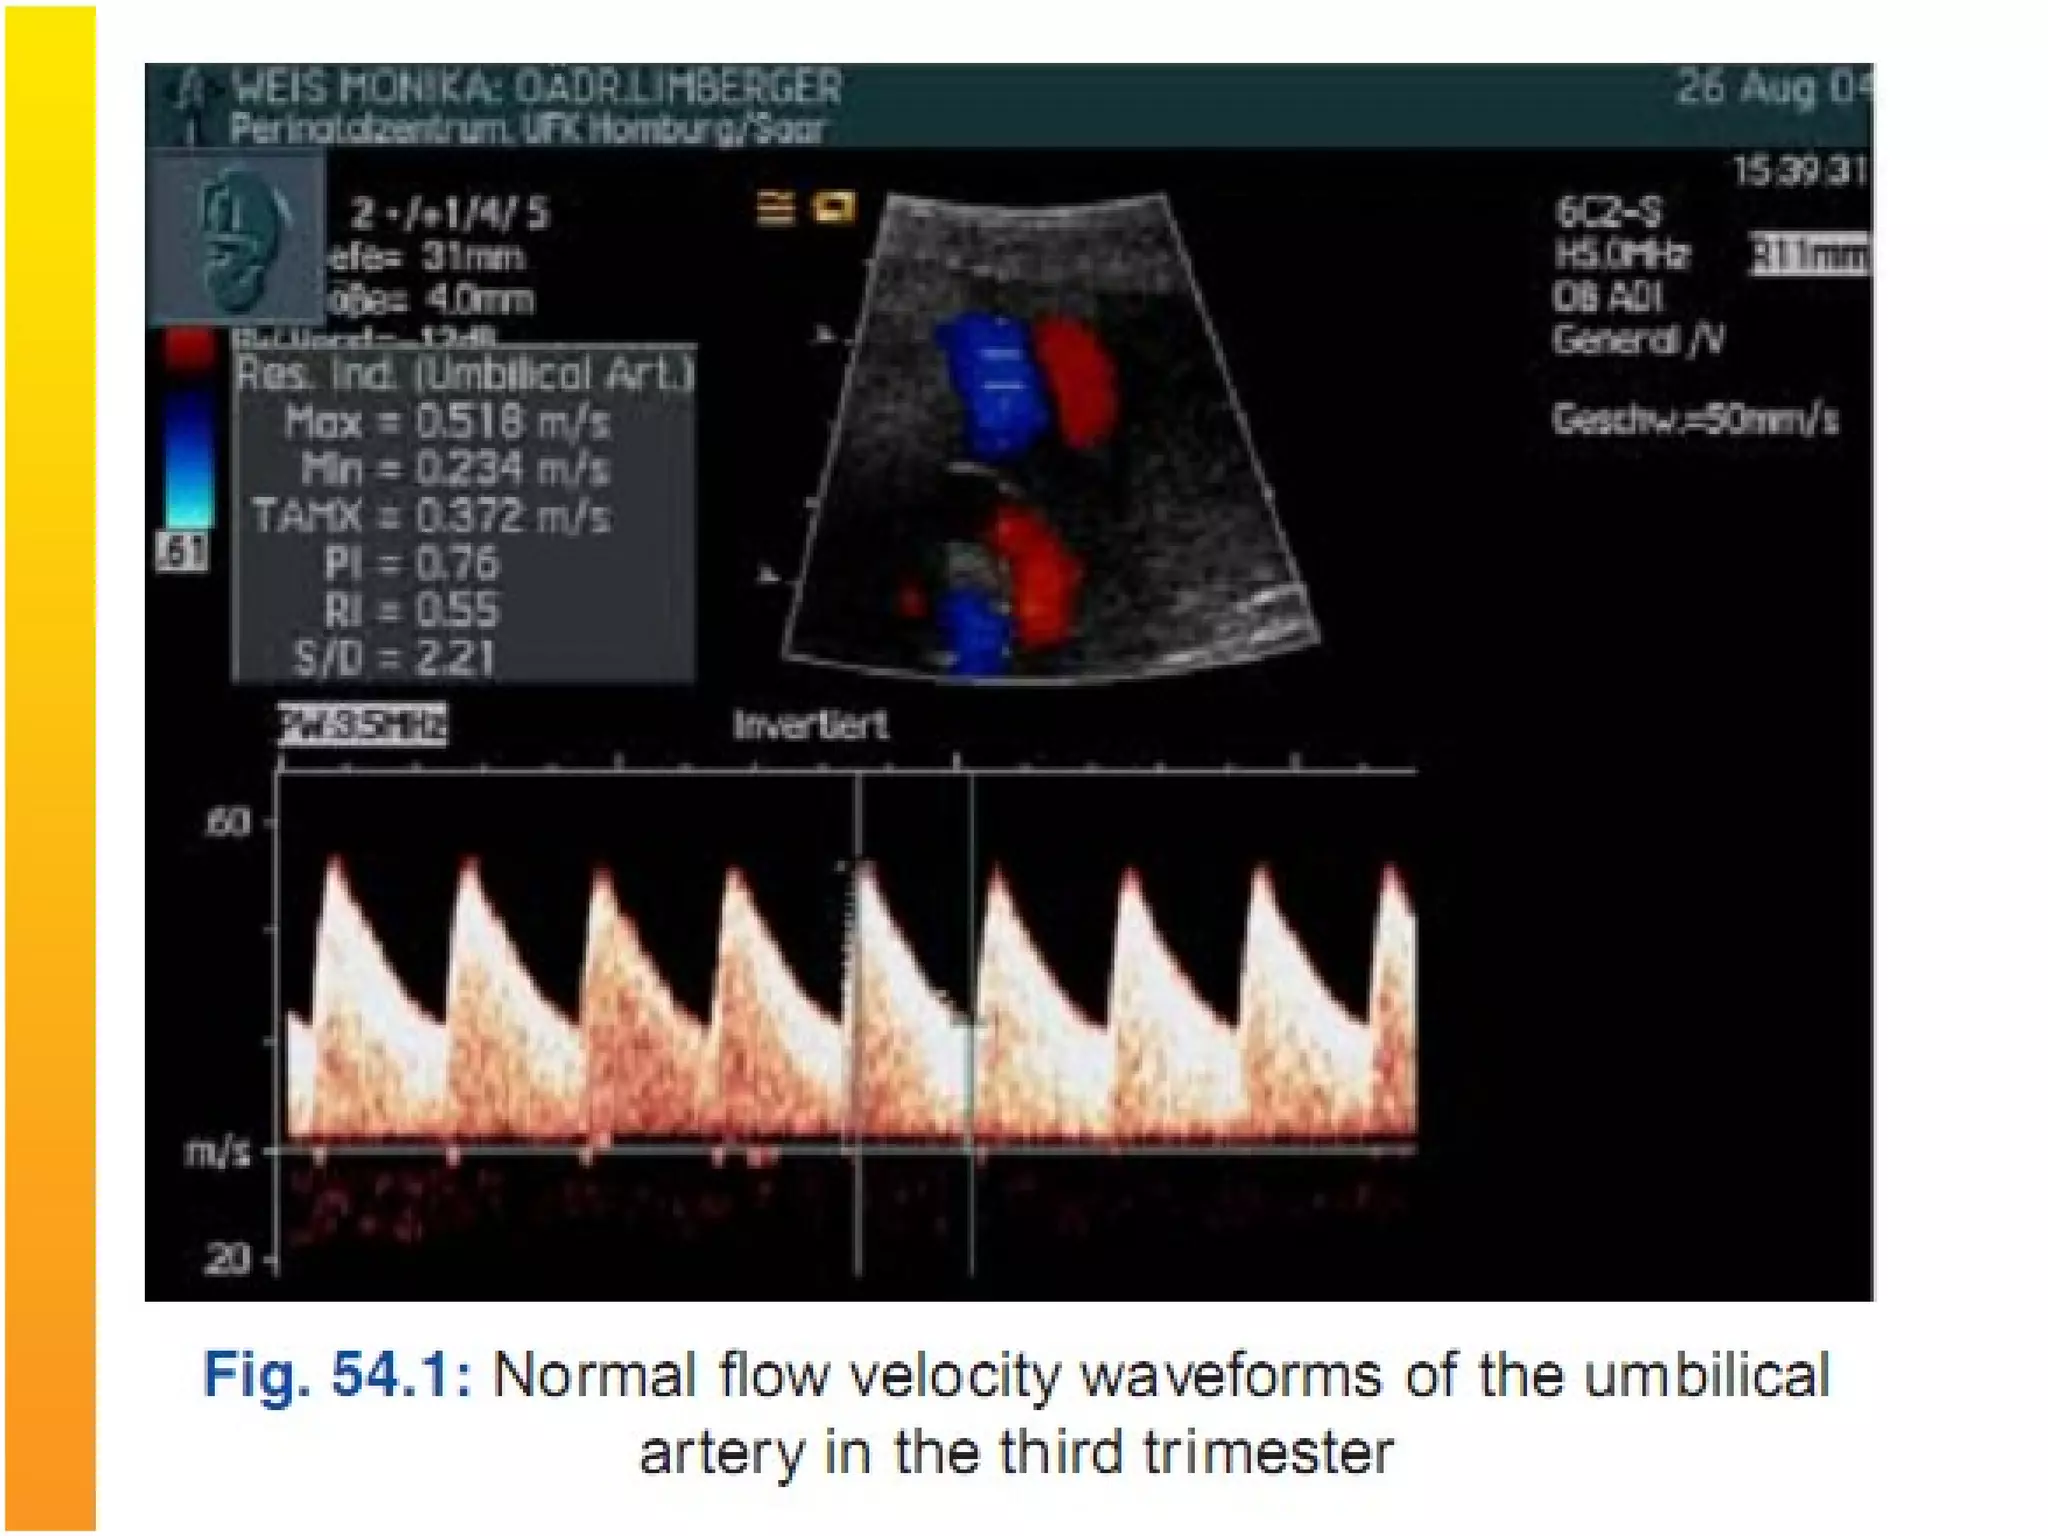

3. Doppler Ultrasonography: doppler flow studies are

important adjuncts to fetal biometry in identifying

the IUGR fetuses at risk of adverse outcome.

Most widely used arterial indices are :

Pulsatility index (PI): Systolic end diastolic peak

velocity / time averaged maximum velocity

Resistance Index(RI): Systolic end diastolic peak

velocity/ systolic peak velocity

Systolic to diastolic ratio(S/D): Systolic peak velocity /

diastolic peak velocity

Umblical Artery doppler- In IUGR there is

increased umblical artery resistance (increased

S/D ratio), absent end diastolic flow and finally

reversed end diastolic flow.

Perinatal mortality rate increases significantly in

fetuses with absent end diastolic flow (9-41%)

and reversed end diastolic flow (33-73%) in

umblical artery.

3. Doppler Ultrasonography:doppler flow studies are important adjuncts to fetal biometry in identifying the IUGR fetuses at risk of adverse outcome. Most widely used arterial indices are : Pulsatility index (PI): Systolic end diastolic peak velocity / time averaged maximum velocity Resistance Index(RI): Systolic end diastolic peak velocity/ systolic peak velocity Systolic to diastolic ratio(S/D): Systolic peak velocity / diastolic peak velocity

Umblical Artery doppler-In IUGR there is increased umblical artery resistance (increased S/D ratio), absent end diastolic flow and finally reversed end diastolic flow. Perinatal mortality rate increases significantly in fetuses with absent end diastolic flow (9-41%) and reversed end diastolic flow (33-73%) in umblical artery.